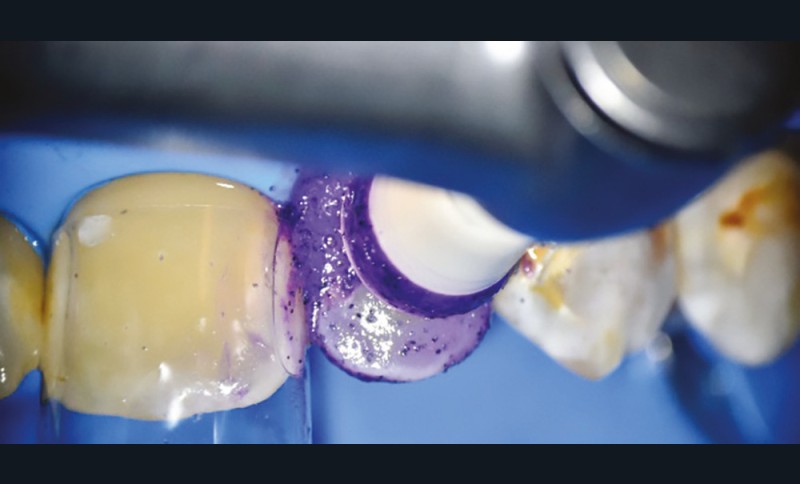

• Traitement micro invasif : il s’agit essentiellement de l’érosion/infiltration (fig. 5), mais une alternative peut également être utilisée pour les mêmes indications : le traitement de micro abrasion (fig. 6). L’indication première de cette technique est d’arrêter la progression des lésions carieuses non cavitaires lors d’une déminéralisation de l’émail (ICDAS 2) ou cavitaires au niveau de l’émail sans déminéralisation de la dentine sous-jacente (ICDAS 3) d’un patient à faible risque carieux.

Le principe d’érosion infiltration consiste à infiltrer par capillarité l’émail déminéralisé avec de la résine. La surface dentaire doit être préalablement traitée par un acide afin d’ouvrir les porosités de surface de l’émail et permettre une meilleure pénétration de la résine. Le processus carieux sera stoppé en bloquant la pénétration des acides cariogènes et la structure dentaire sera préservée.

Cette technique est réalisée en une seule séance clinique, et présente l’avantage d’être peu invasive et indolore. Cependant, le problème de l’accessibilité dans les lésions proximales est un facteur qui limite l’utilisation de ces thérapeutiques. Le recours à un élastique orthodontique quelques jours avant la mise en place de la résine est une solution intéressante pour améliorer l’accessibilité et traiter les lésions de déminéralisation en proximal. Aujourd’hui, ces thérapeutiques sont également utilisées dans le traitement esthétique des taches blanches vestibulaires de l’émail, la mise en place du produit étant facilitée dans ces situations cliniques.